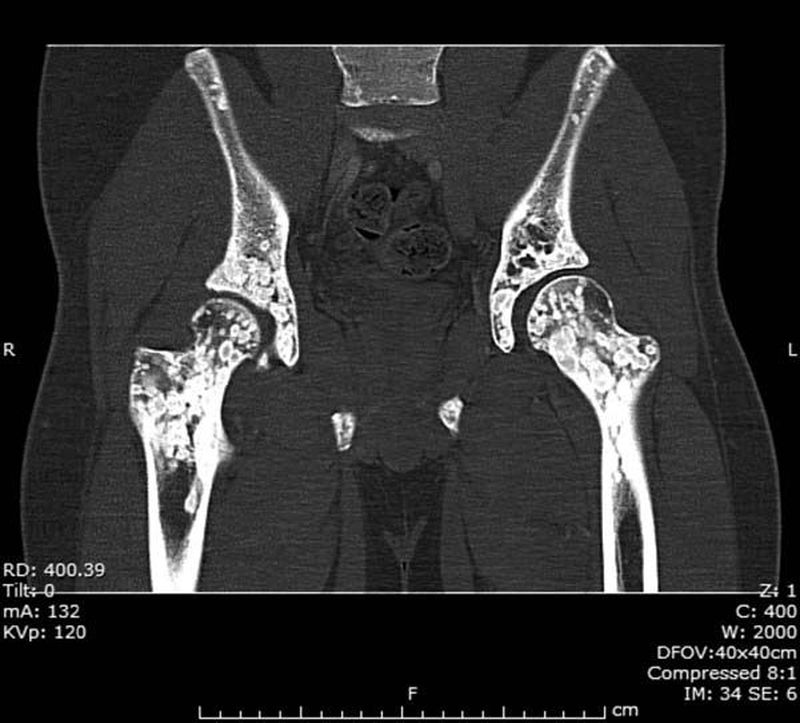

A 17-year-old boy is found to have these asymptomatic bone lesions on CT scan. A)Bone metastases B)Paget’s disease C)Osteogenesis imperfecta D)Osteopoikilosis

D) ;-)